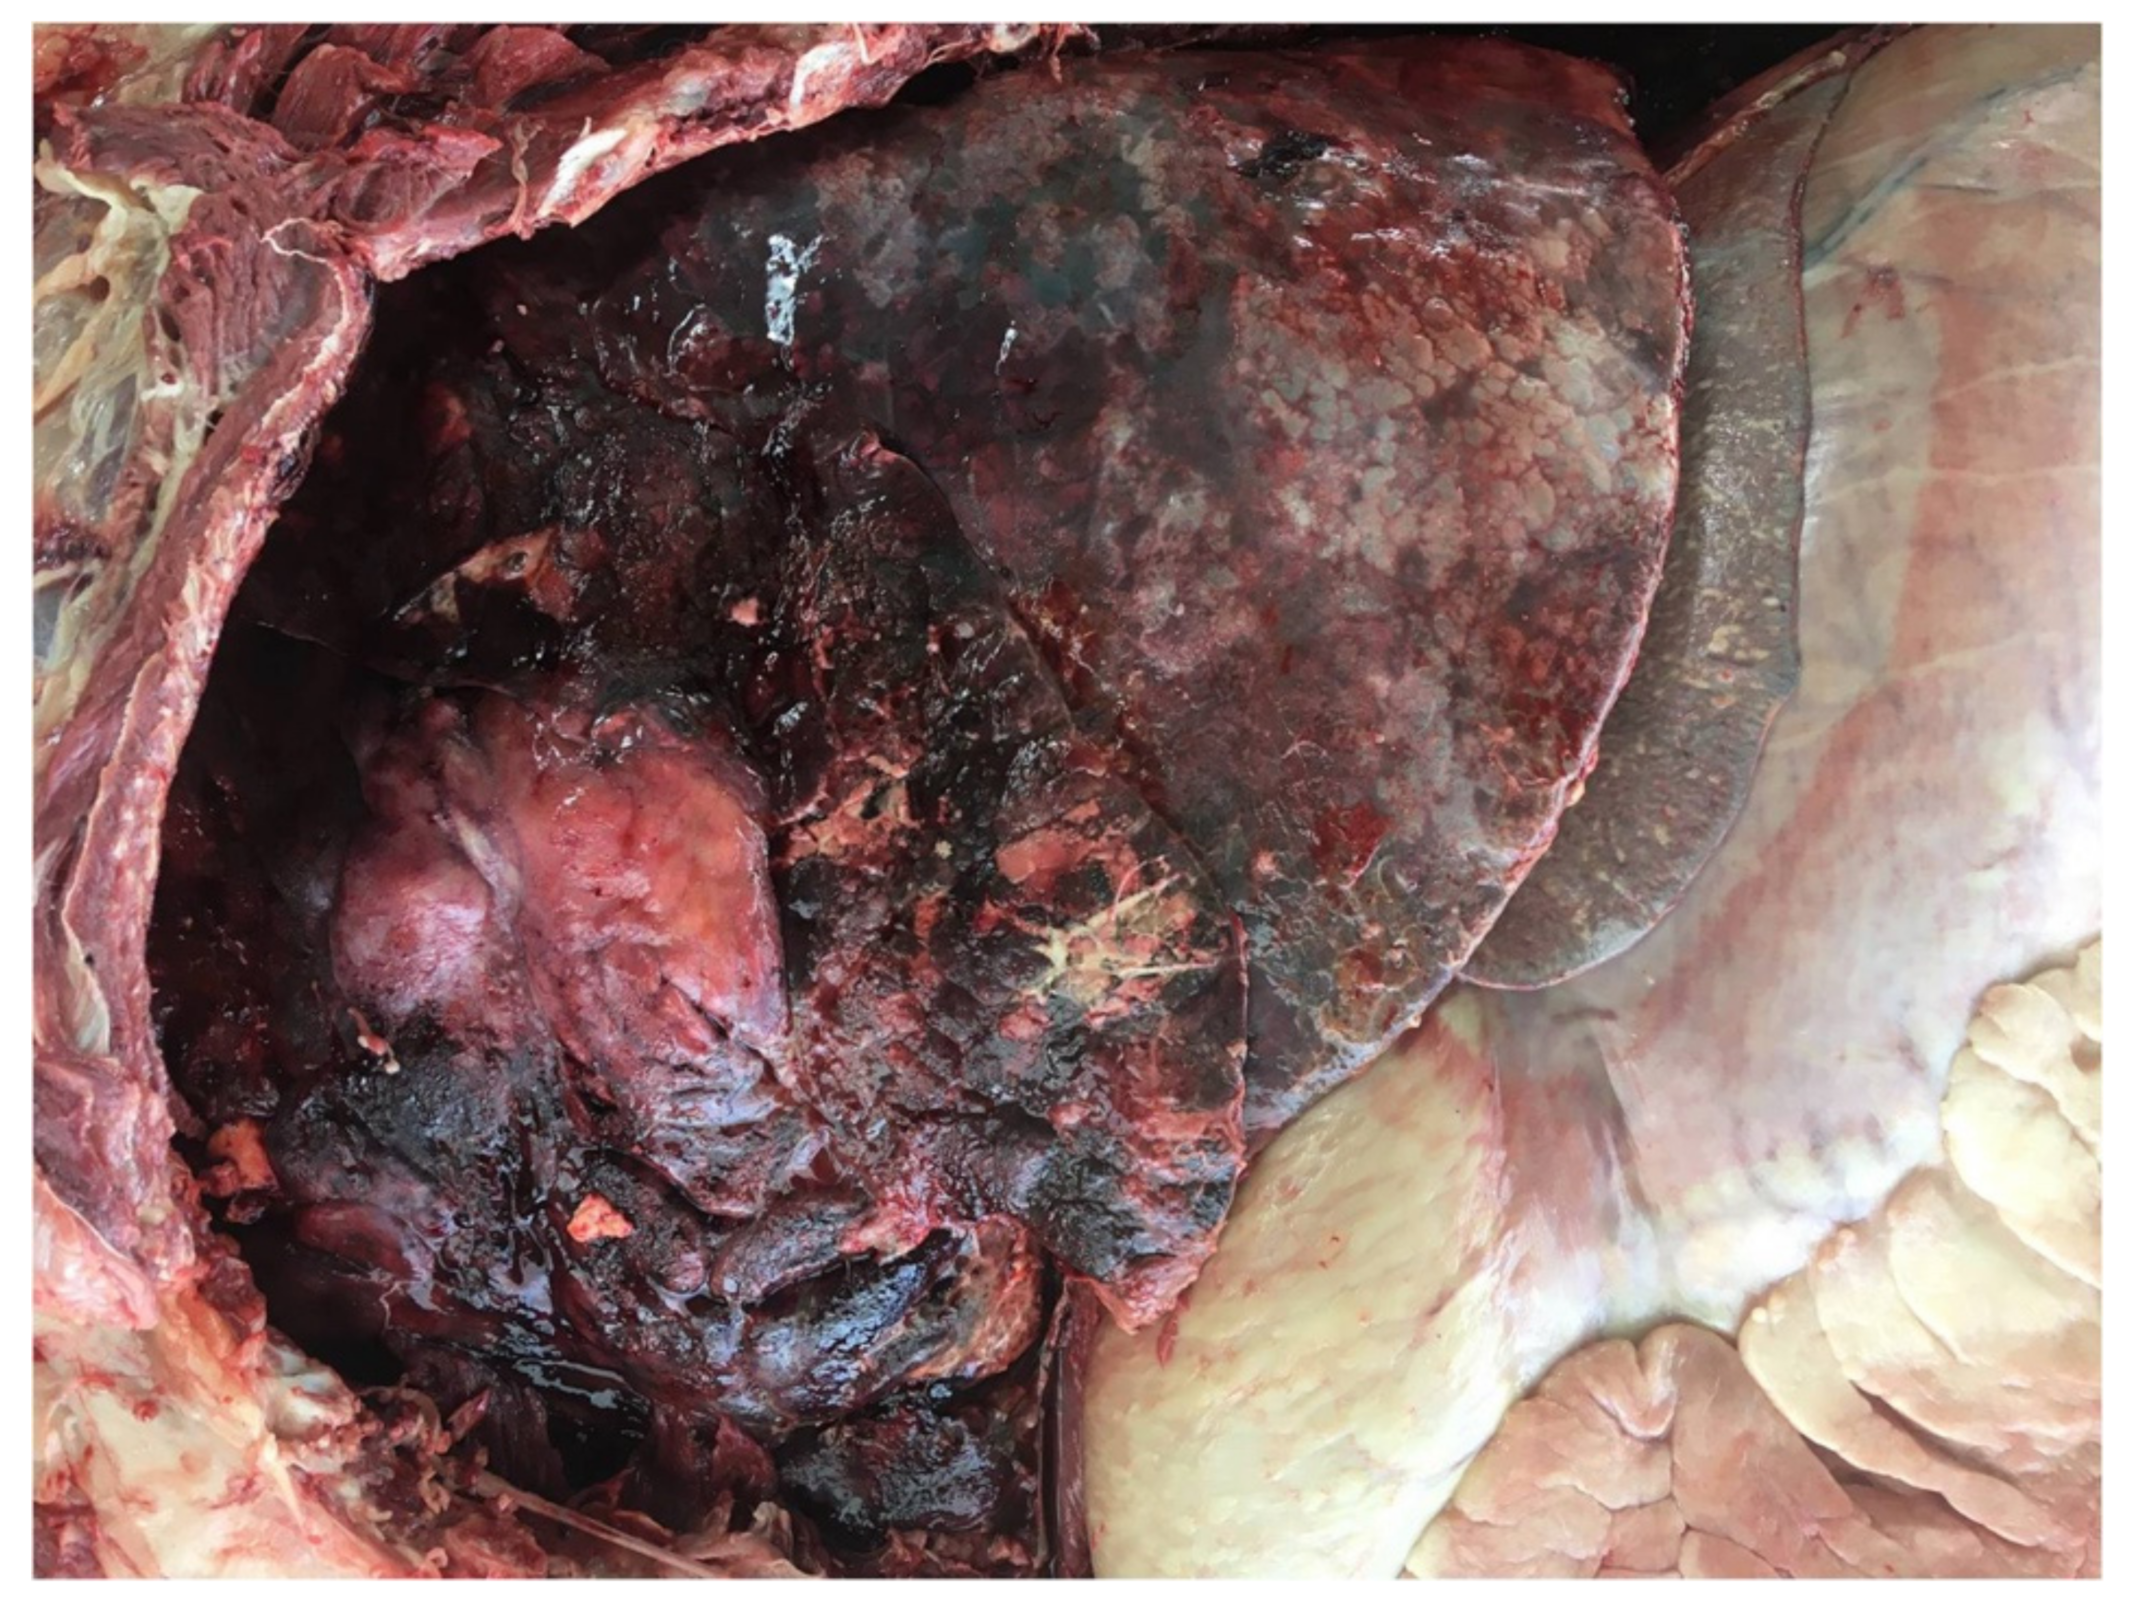

The cranioventral regions of both lungs were severely hyperemic and firm at palpation, with a discrete amount of fibrin adhering to the pleural sheets (Figure 2). Tracheobronchial and mediastinal lymph nodes were markedly enlarged, hyperemic and edematous in the cut section.

Figure 2. Left lung. Pleuritis and bronchopneumonia. Cranial and cardiac lobes appear congested and covered by discrete amounts of fibrin.